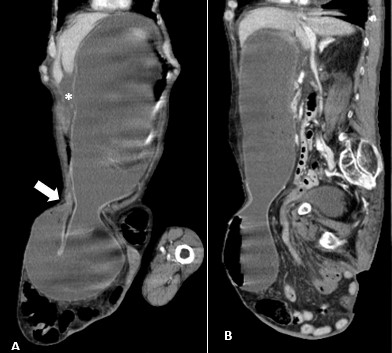

A tangential abdominal radiography was obtained, in this context, and a gas level on the non-dependent portion of the abdomen was identified (Figure 1). This finding raised the suspicion of pneumoperitoneum and, therefore, a CT was performed. On CT, a markedly distended stomach, as well as a distended oesophagus and free abdominal fluid were identified, implying an obstructive event (Figure 2). The inferior portion of the stomach and some intestinal loops were contained on the right inguinoscrotal hernia, making this the most probable cause for the obstruction (Figure 3).

Figure 3: Marked gastric distension, with inferior part of gastric body herniated through inguinal hernia, and with transition point at the level of pylorus (A, white arrow). Free abdominal fluid is also present (A,*).